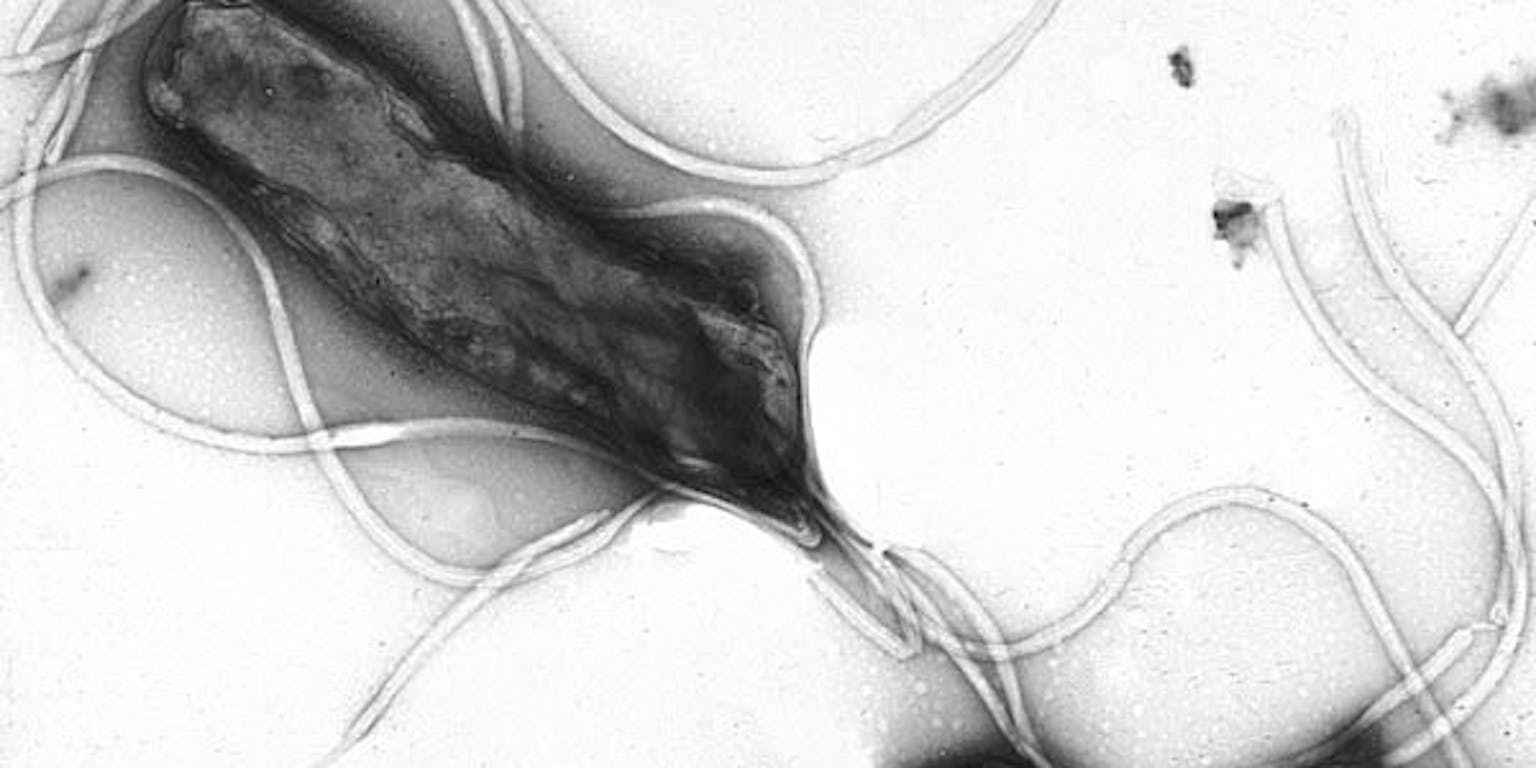

Zuurremmers afgenomen

Helicobacter pylori is een bijzondere bacterie. “De meeste bacteriën gaan dood in het zure milieu van de maag, maar deze kan er tegen. Hij nestelt zich in het maagslijmvlies en als reactie hierop vormt je maag meer maagzuur. De bacterie maakt echter stoffen aan die de functie van de cellen van de maagwand aantasten. Hierdoor krijg je uiteindelijk minder maagzuur. Dat is juist de ellende, want daardoor hebben mensen ook geen pijn meer, terwijl de bacterie er nog zit. Uiteindelijk kun je zo maagkanker krijgen. De speciale antibioticakuur doodt de bacterie en het maagslijmvlies herstelt zich dan weer. Sinds we de bacterie gericht kunnen uitroeien bij mensen is de hoeveelheid zuurremmers en Rennies die gebruikt wordt, drastisch afgenomen. Maar je kunt ook last hebben van brandend maagzuur zonder de bacterie.”